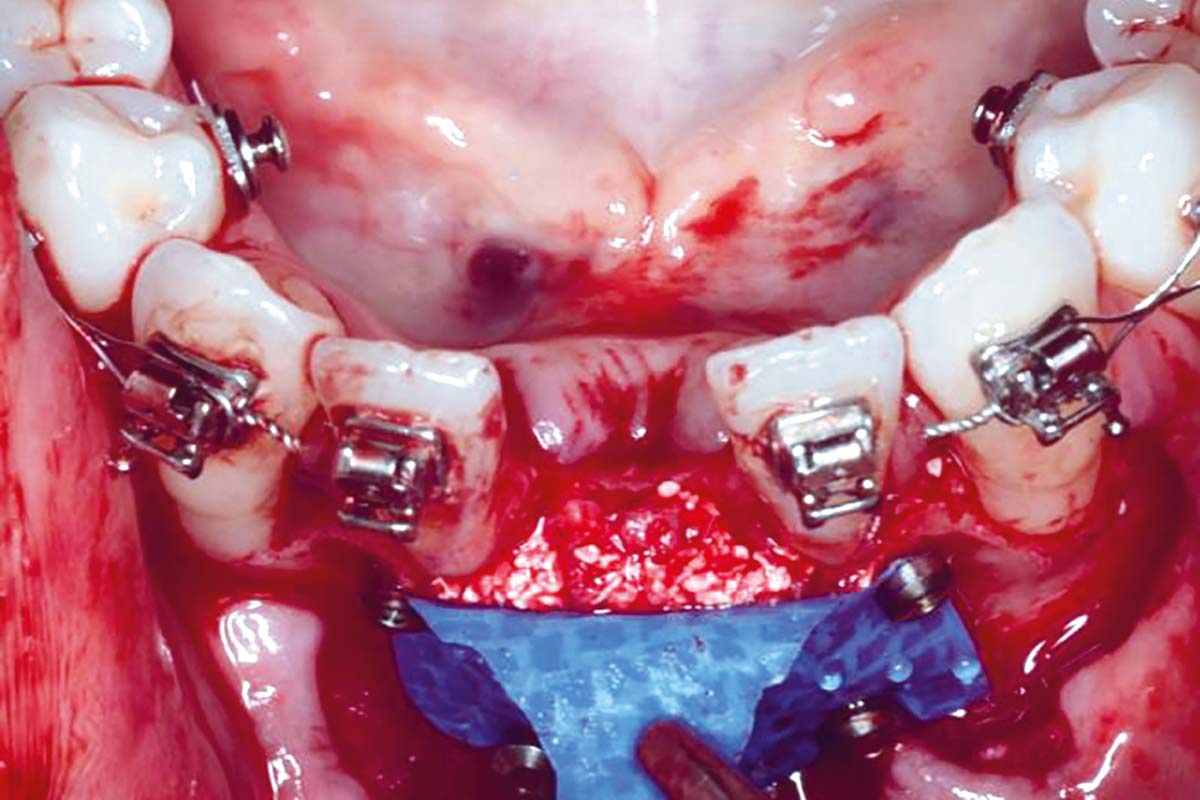

Regenerative corticotomy to compensate lower incisor malocclusion with cerabone® and mucoderm®

Initial view of the clinical case: Class III malocclusion

Treatment plan: Regenerative corticotomy (PAOO)